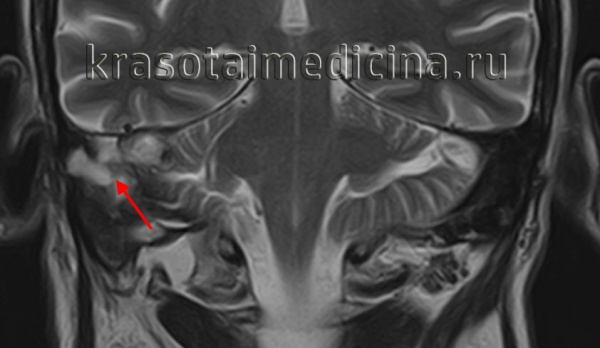

КТ височных костей. Деструкция сосцевидного отростка, сосцевидной пещеры, пирамиды и среднего уха правой височной кости, обусловленная холестеатомой

МРТ головы. Гиперинтенсивный сигнал в области сосцевидной пещеры, сосцевидного отростка и пирамиды правой височной кости (холестеатома)